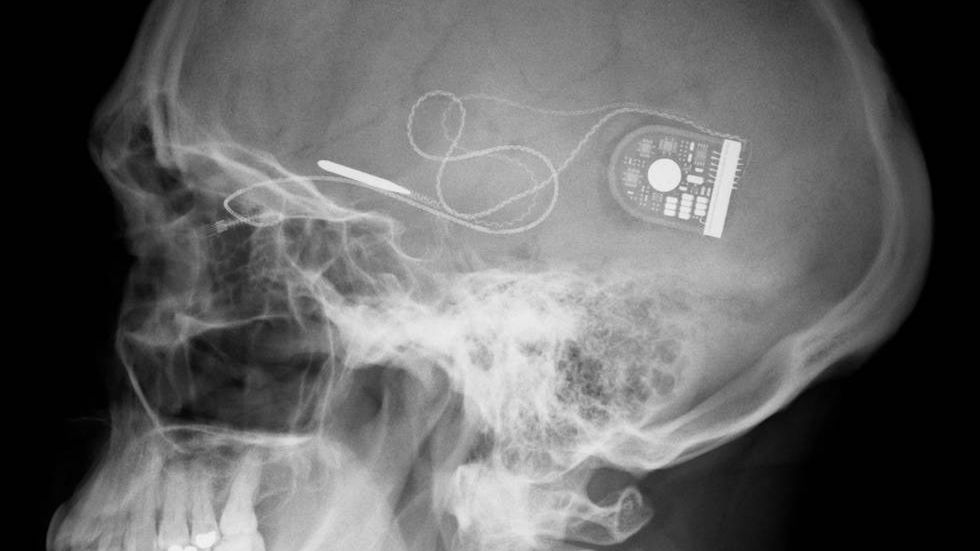

Sposobem na realizację tego celu ma być urządzenie, które dzięki miniaturowym rozmiarom będzie można podpiąć do układu nerwowego. Urządzenie będzie na bieżąco monitorować stan organizmu i zachodzące w nim procesy, a następnie w taki sposób stymulować układ nerwowy, by – np. poprzez zwiększone wydzielanie różnych hormonów - szybciej leczyć różne dolegliwości. Na liście, oprócz przywracania prawidłowej pracy poszczególnych narządów znalazły się m.in. stres pourazowy, padaczka, depresja, choroby zapalne w tym zapalenie stawów.

© Fot. DARPA